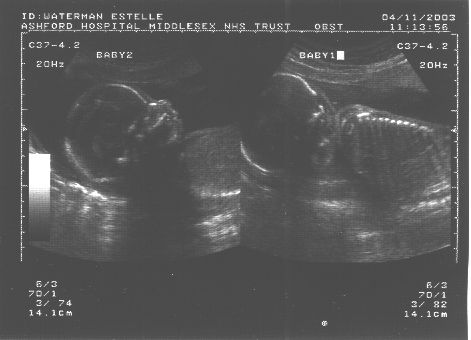

We weren't expecting quite such a surprise ourselves! TWINS!

Pics:

Both together:

Identical? Apparrently not. If you look closely at the 3rd

picture, you can see they're in seperate sacks. That means they're

ALMOST certainly fraternal (non-identical) twins.